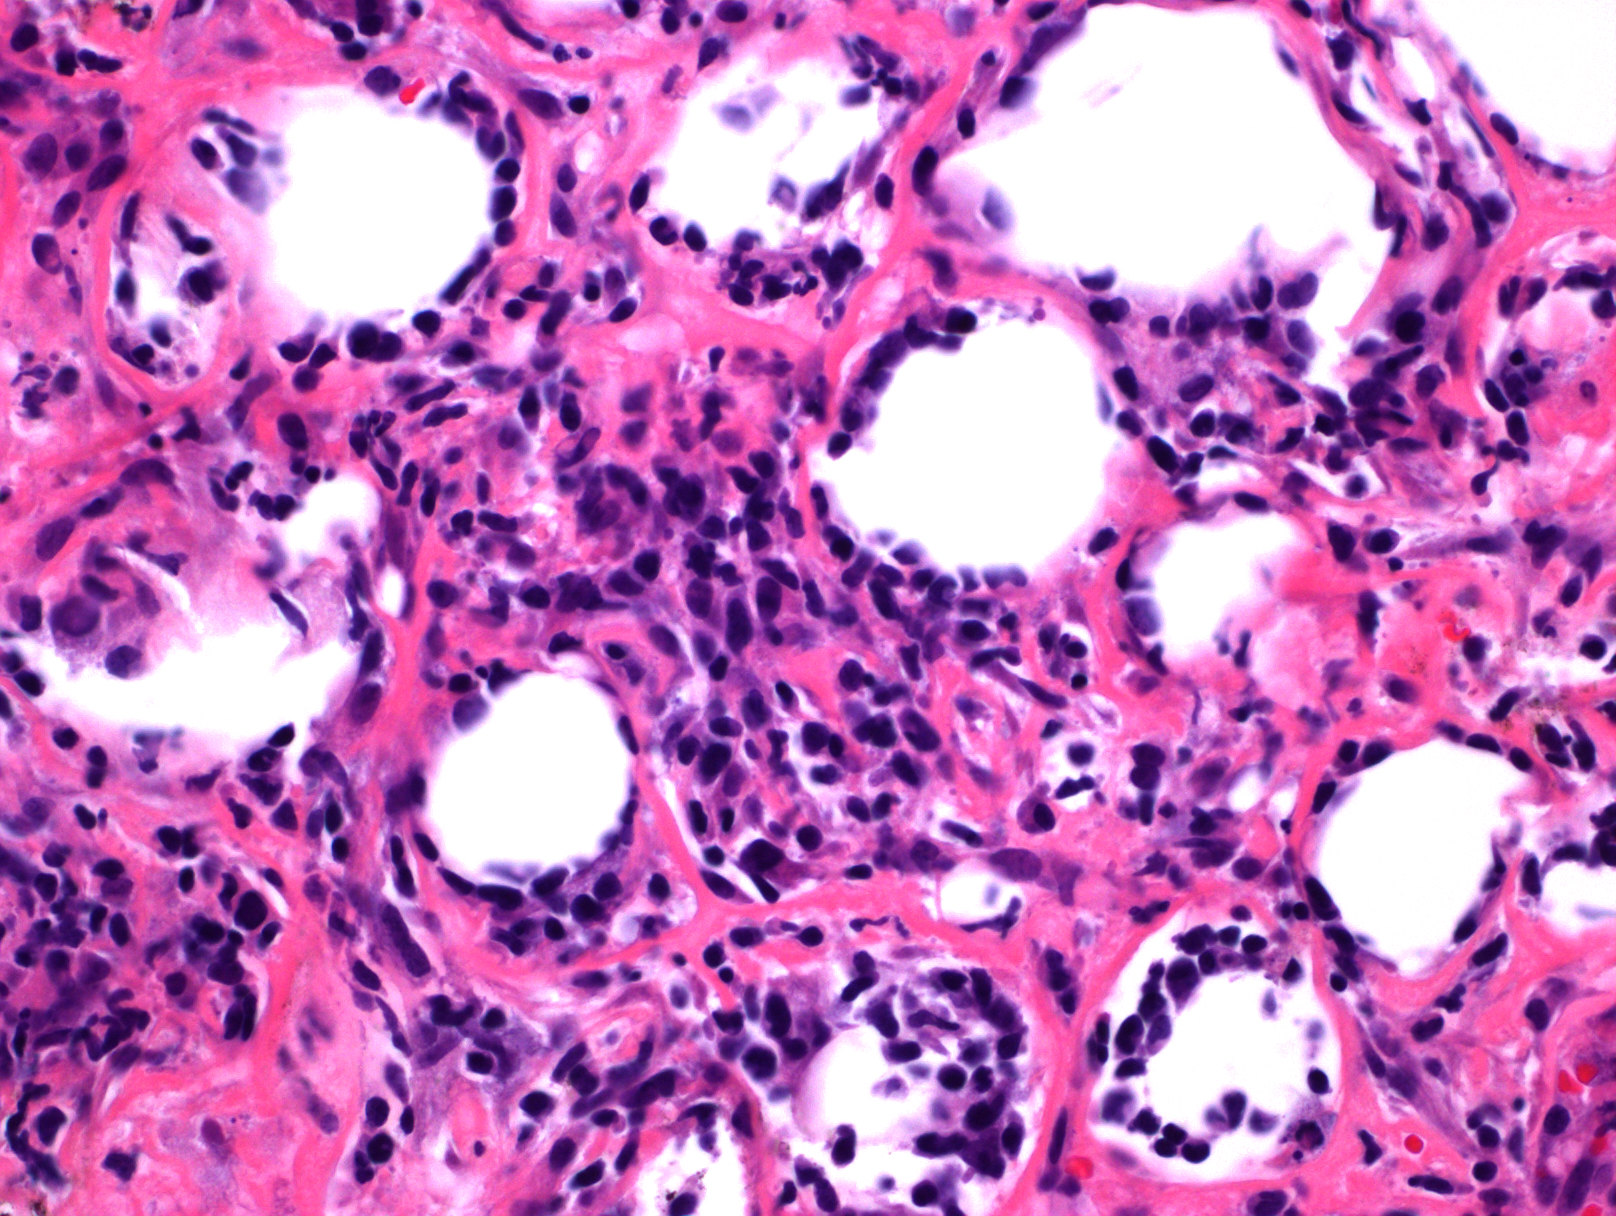

3. 肿瘤细胞大小以病例而定,通常小到中等,也可中到大,但具体某一病例细胞大小较一致,核不规则深染。常混有组织细胞,甚至形成局部肉芽肿样改变,其它炎性细胞(如浆细胞)缺乏或罕见。